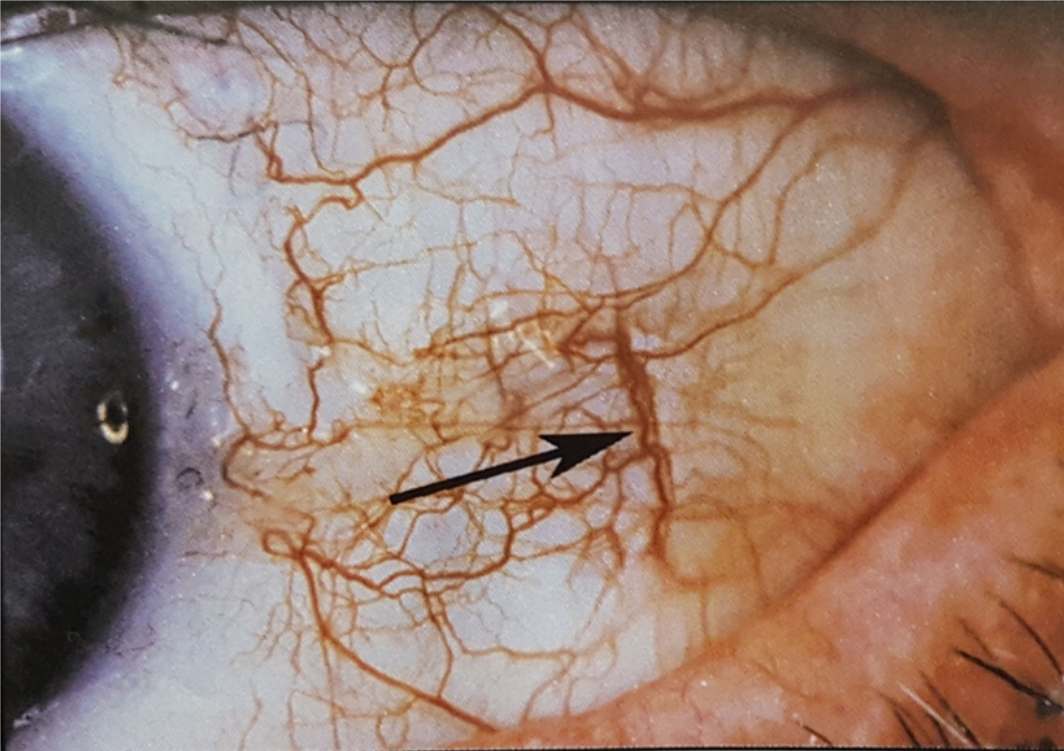

Sinal: Veias Paralelas Grossas

Indicação Física: Pode sugerir deposição de placas nas artérias, indicando a necessidade de atenção à saúde vascular e cardíaca.